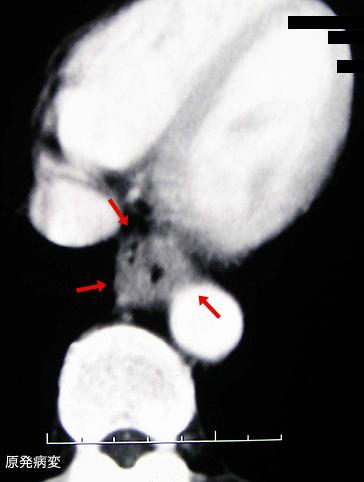

clasificación del pacienteTumor Epitelial Maligno/Carcinoma a Células Escamosas

parte(separada por órganos)esófago/inferior

método de exámenTAC

clasificación ectoscópica de tumoresTipo 3(Tipo ulcerado de bordes infiltrados)/

diámetro mayor del tumor35 - 40

grado de penetracións(a)